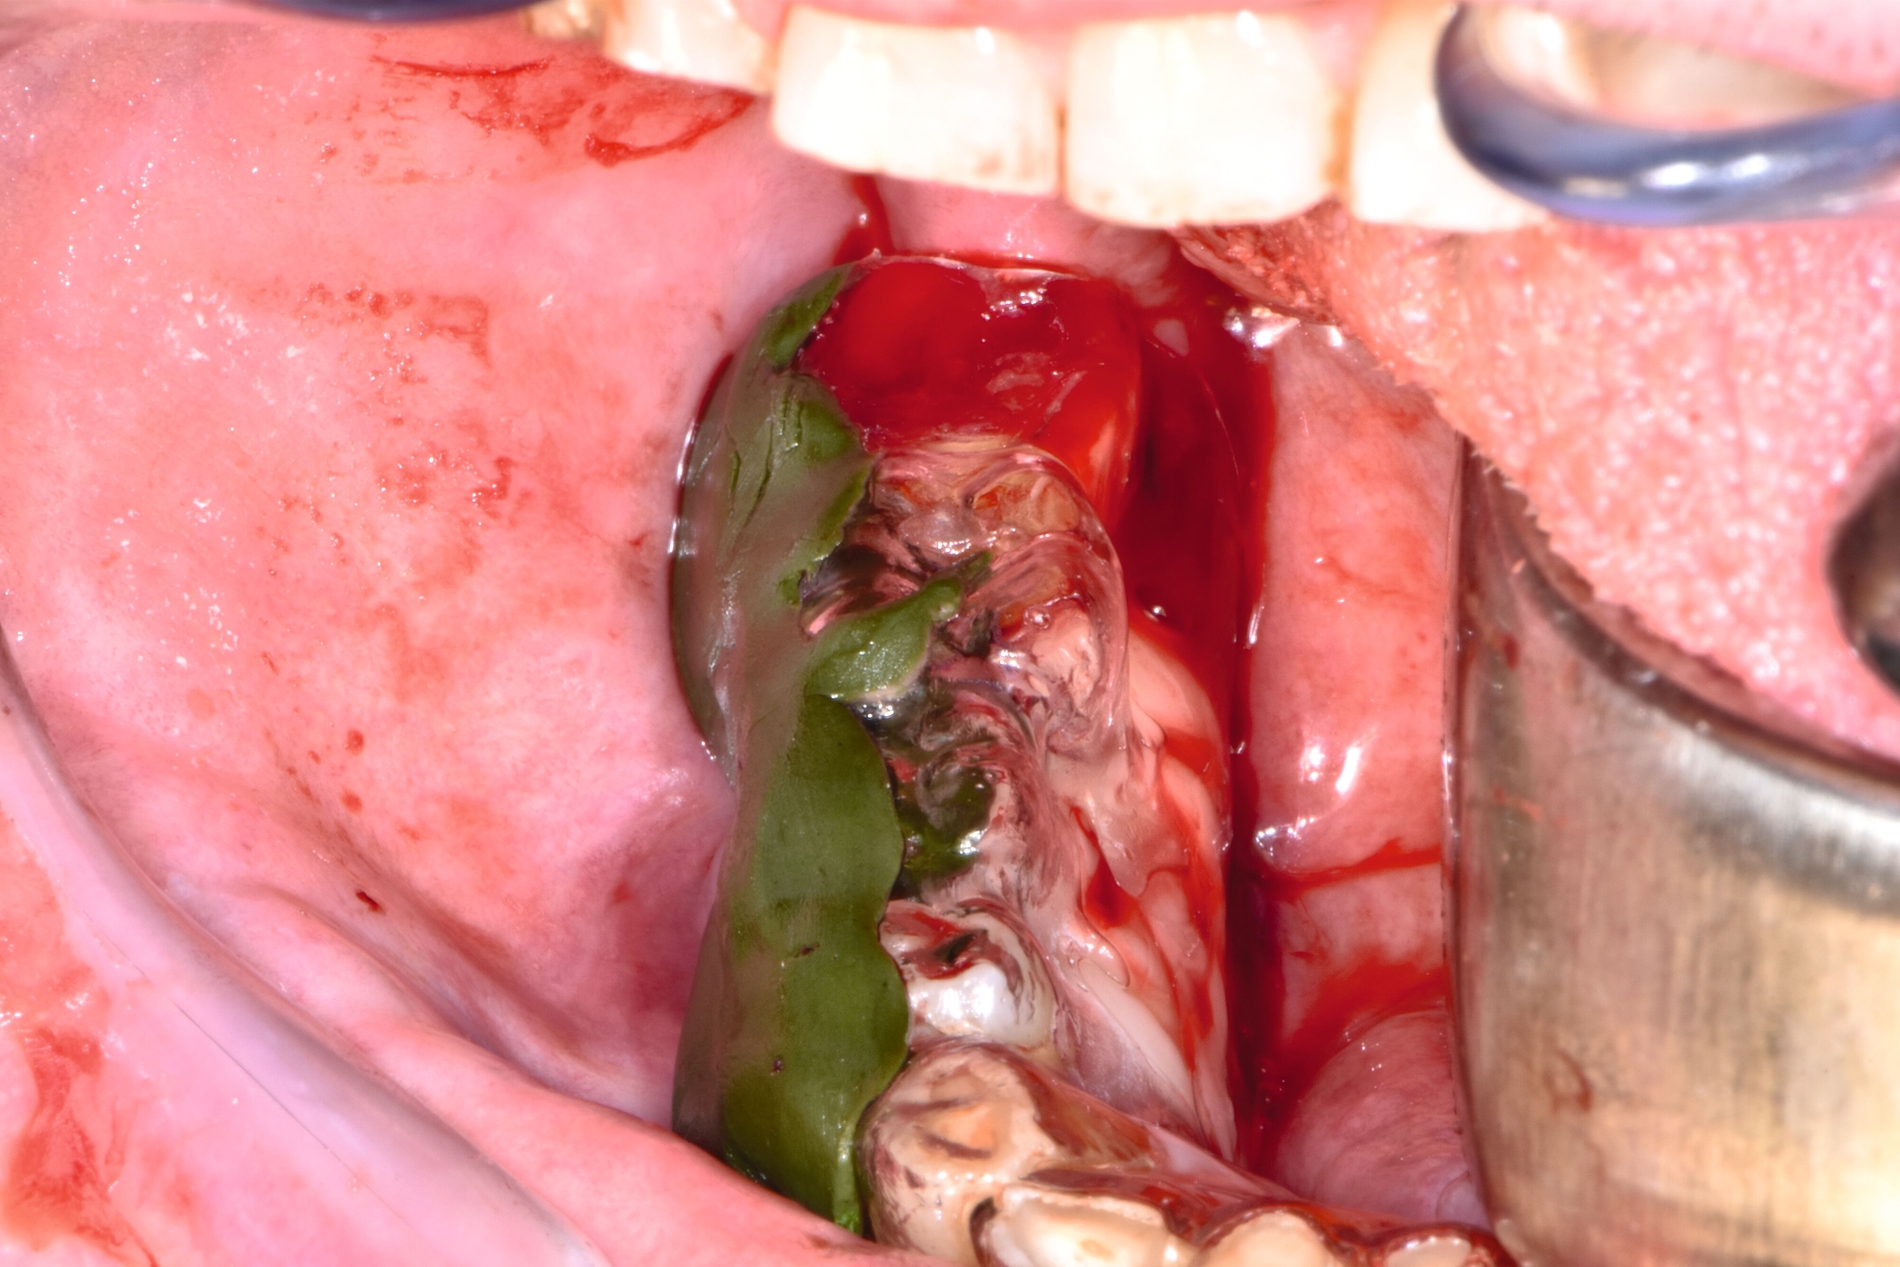

Therapeutisch erfolgte eine gezielte Sequestrotomie und nur zwei Zahnentfernungen. Auf eine plastische Deckung wurde bewusst verzichtet. Stattdessen wurde Platelet-Rich Fibrin (PRF) auf die Wundfläche appliziert und mit einer Verbandplatte geschützt. Unter vorübergehender enteraler Ernährung über eine Magensonde zeigte sich eine nahezu vollständige Schleimhautregeneration innerhalb weniger Wochen. Eine kleine Restläsion in Regio 44 lingual heilte unter lokaler Therapie mit Chlorhexidin und einer Occlusivpaste vollständig ab. Eine Kontrollszintigrafie nach sechs Monaten bestätigte die weitgehende Ausheilung.

Im beschriebenen Fall wurde nach der Sequestrotomie, die eine ausgedehnte Knochenwundfläche hinterließ, ergänzend PRF appliziert, um die Weichgewebsheilung zu fördern und zugleich auf eine plastische Deckung verzichten zu können. Der Einsatz von PRF bot dabei eine biologische Unterstützung der sekundären Schleimhautheilung und ermöglichte eine nahezu komplikationslose Wundregeneration trotz der großflächigen Exposition. Klinische Studien belegen eine beschleunigte epitheliale Regeneration und eine geringere Inzidenz von Wunddehiszenzen nach PRF-Anwendung [Temmerman, 2016]. Ein solcher Heilungsverlauf wäre bei Medikamenten-assoziierten oder Strahlen-bedingten Osteonekrosen in der Regel nicht zu erwarten, da dort (unter anderem) eine persistierende Gefäßschädigung und eine chronische Ischämie bestehen. Im Gegensatz dazu ist die Durchblutung bei der Herpes-Zoster-assoziierten Osteonekrose nach Abklingen der akuten Vaskulitis meist wiederhergestellt, was eine weitgehend physiologische Regeneration des Gewebes ermöglicht.